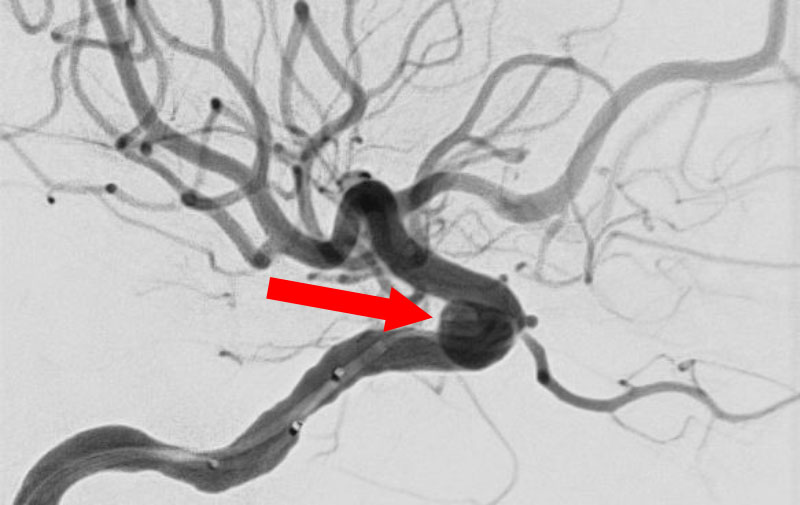

'25年10月

くも膜下出血

前交通動脈瘤破裂

40代

大阪府の病院

No.1589 手術前

No.1589 手術中

No.1589 手術後